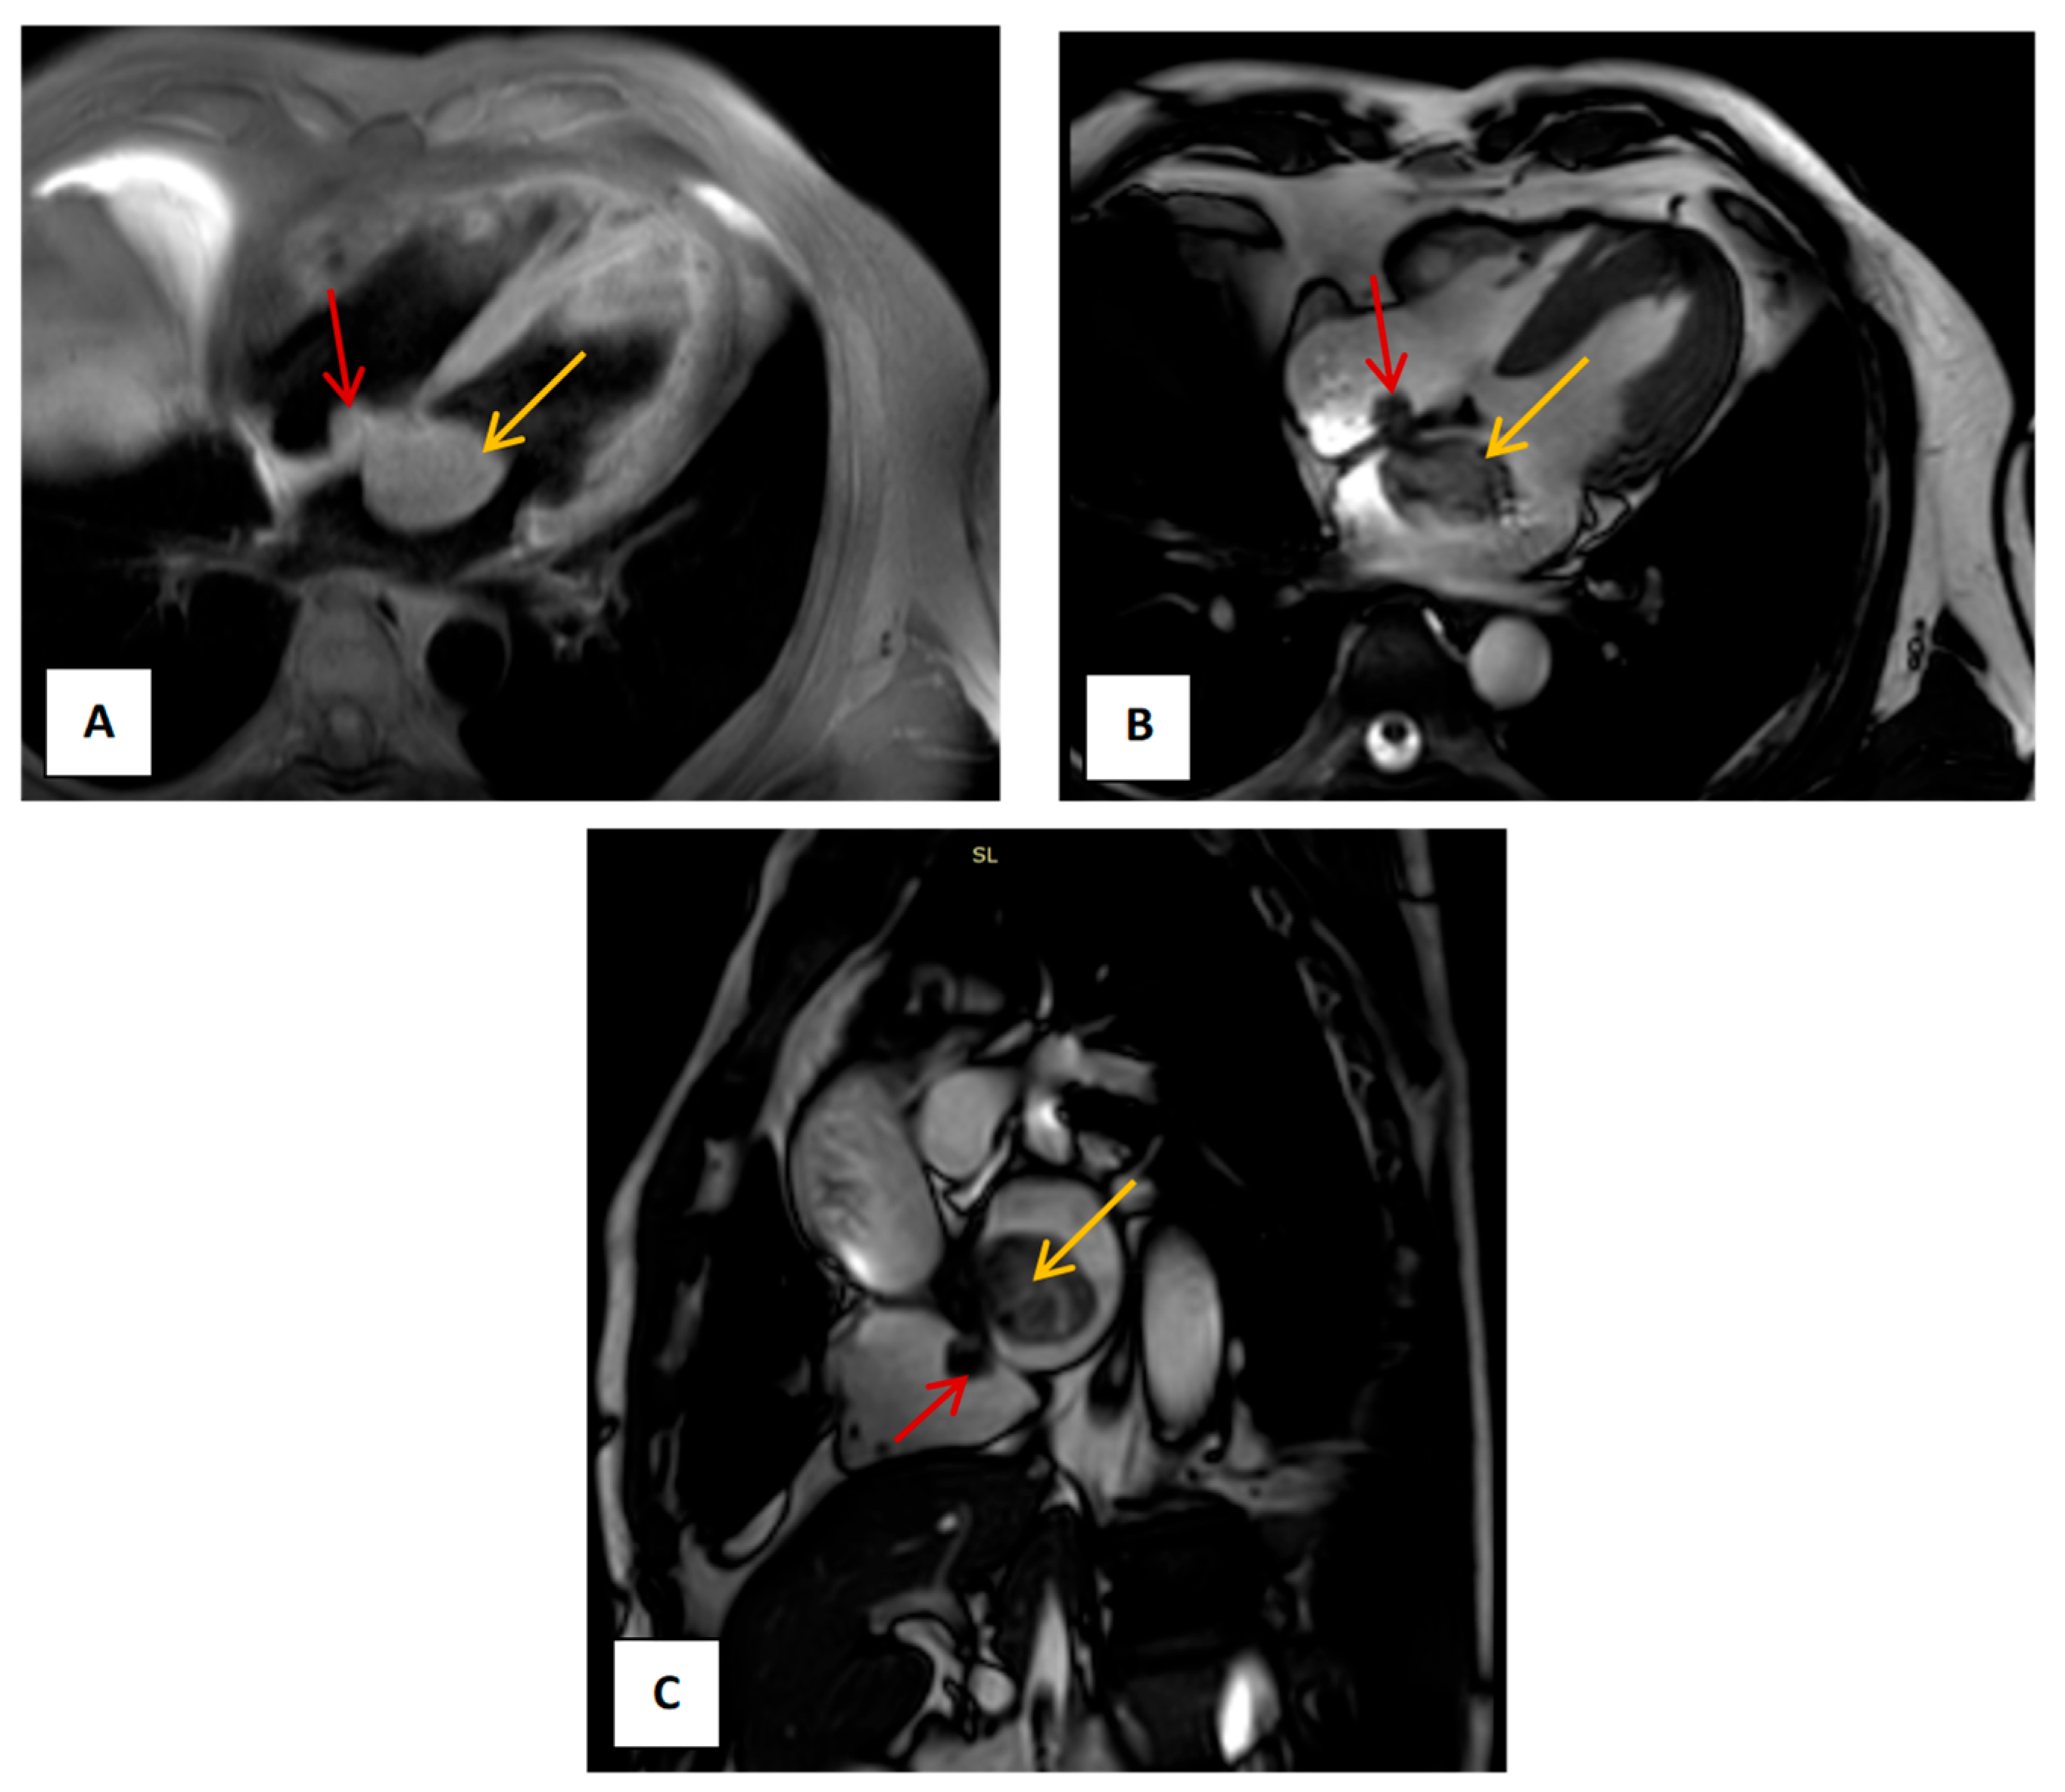

2. Case Presentation